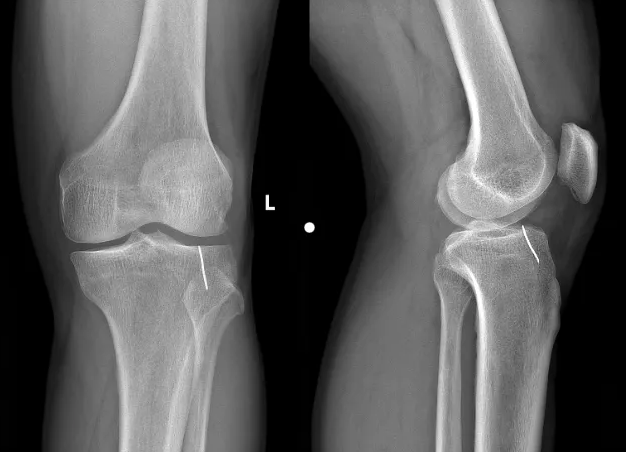

据患者回忆,事发时他正在家中操作割草机,突然感觉膝盖一阵刺痛,低头发现膝关节前下方被异物划开一道约2cm的伤口。随后他立即前往附近医院就诊,进行了常规清创包扎处理。本以为只是简单的皮外伤,没想到几天后,膝关节的疼痛不仅没有缓解,反而出现了明显的屈伸活动受限,就连走路都变得困难。通过X光检查发现:膝关节内竟然藏有金属异物,若不及时取出,可能引发关节感染、软骨损伤等严重后果。

金合主任医师结合影像学资料,详细询问病史后,安排患者住院治疗。在此过程中,完善了膝关节CT检查,准确锁定了异物位置——铁钉已嵌入胫骨,其中一端已进入关节腔。考虑到异物位置特殊,开放手术创伤大、恢复慢,科室团队经过评估、讨论,决定采用膝关节镜手术取出异物。